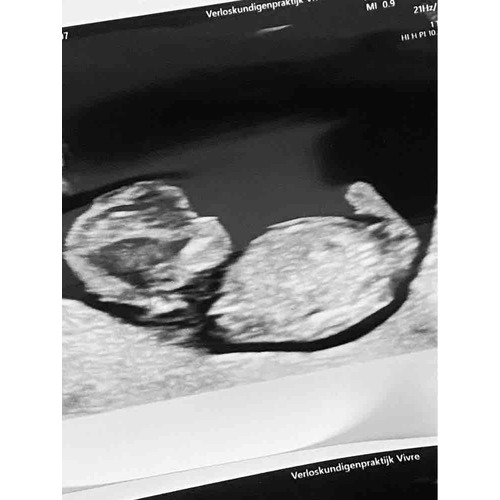

11+6 zou denken een meisje. Als het echt de NUB is haha.

Ik zou zeggen een meisje. Het gaat eerder richting -30掳 dan +30掳 馃槀

Ja dat is zo, neigt meer naar meisje dan.. nou... ben benieuwd!